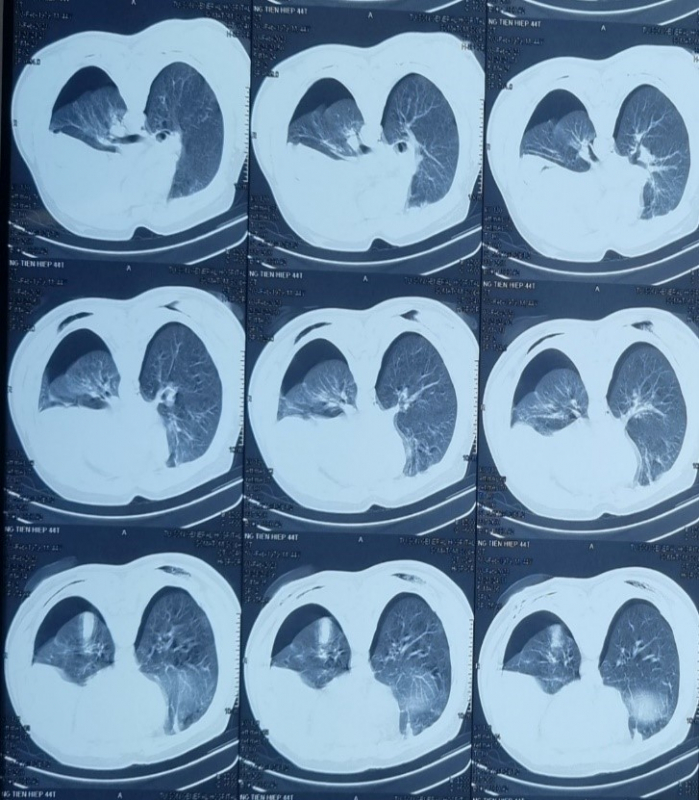

Lúc này cách vụ tai nạn 2 tiếng, bệnh nhân rơi vào tình trạng lơ mơ, da niêm mạc nhợt, khó thở, mạch nhanh nhỏ. Kết quả chụp cắt lớp vi tính lồng ngực tràn khí - tràn dịch khoang màng phổi trái mức độ nhiều, tràn khí màng phổi phải.